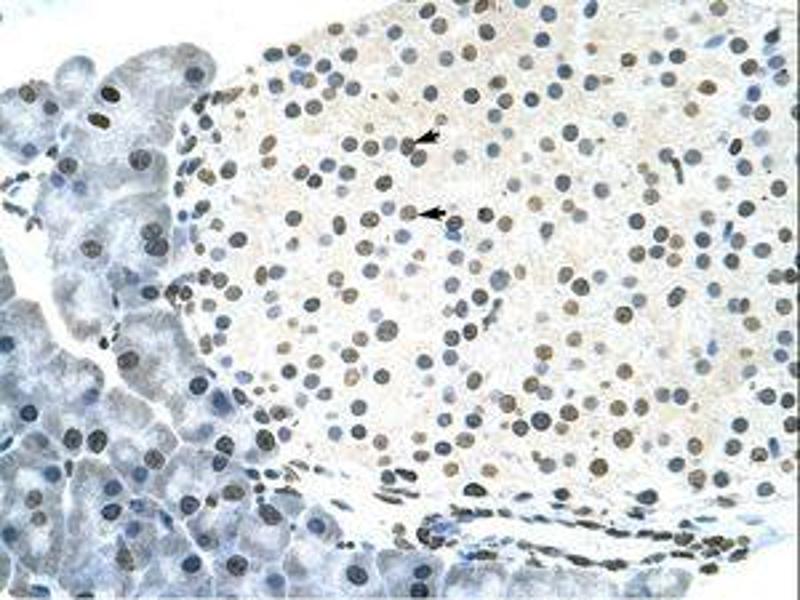

- Approved: IHC, WB (1.25 μg/mL)